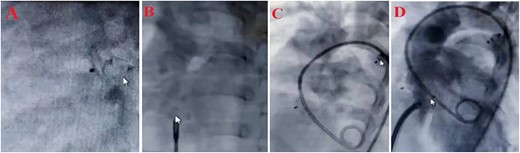

Treatment steps (A) close PDA by Amplatzer ADO II type AGA, size 5–6, (B) close ASD by Amplatzer Septal Oclotec size 15, (C) after closing PDA and ASD, D: close VSD by Amplatzer membranous, lifetec type symetric، size 12, (D) echocardiography four-chamber view after intervention.

Since ASD, PDA, VSD, and pulmonary hypertension were diagnosed; it was decided to perform an interventional heart catheterization. For this purpose, PDA was closed in one step using Amplatzer ADO II type AGA, size 5–6, and then Amplatzer Septal Occluder size 15 was used to close ASD. Finally, the patient was discharged after the first stage treatment process. Six months later, a successful therapeutic interventional closure of the VSD was performed using Lifetech Symmetric Amplatzer membranous size 12 mm. Due to the lack of access to the coil, the smallest and most suitable device was used for the patient. After the treatment process, Echocardiography was used to show the position of ASD amplatzer and VSA amplatzer and there was no residual in VSD and ASD, and complications in the integrity of the aortic valve (without Aortic regurgitation or Aortic stenosis) (Fig. 1). Finally, the patient was discharged with a good general condition and no complications from open heart surgery. The treatment was successfully completed within 3 days of hospitalization. Therefore, the short length of stay in a public hospital led to a significant reduction in patient costs.